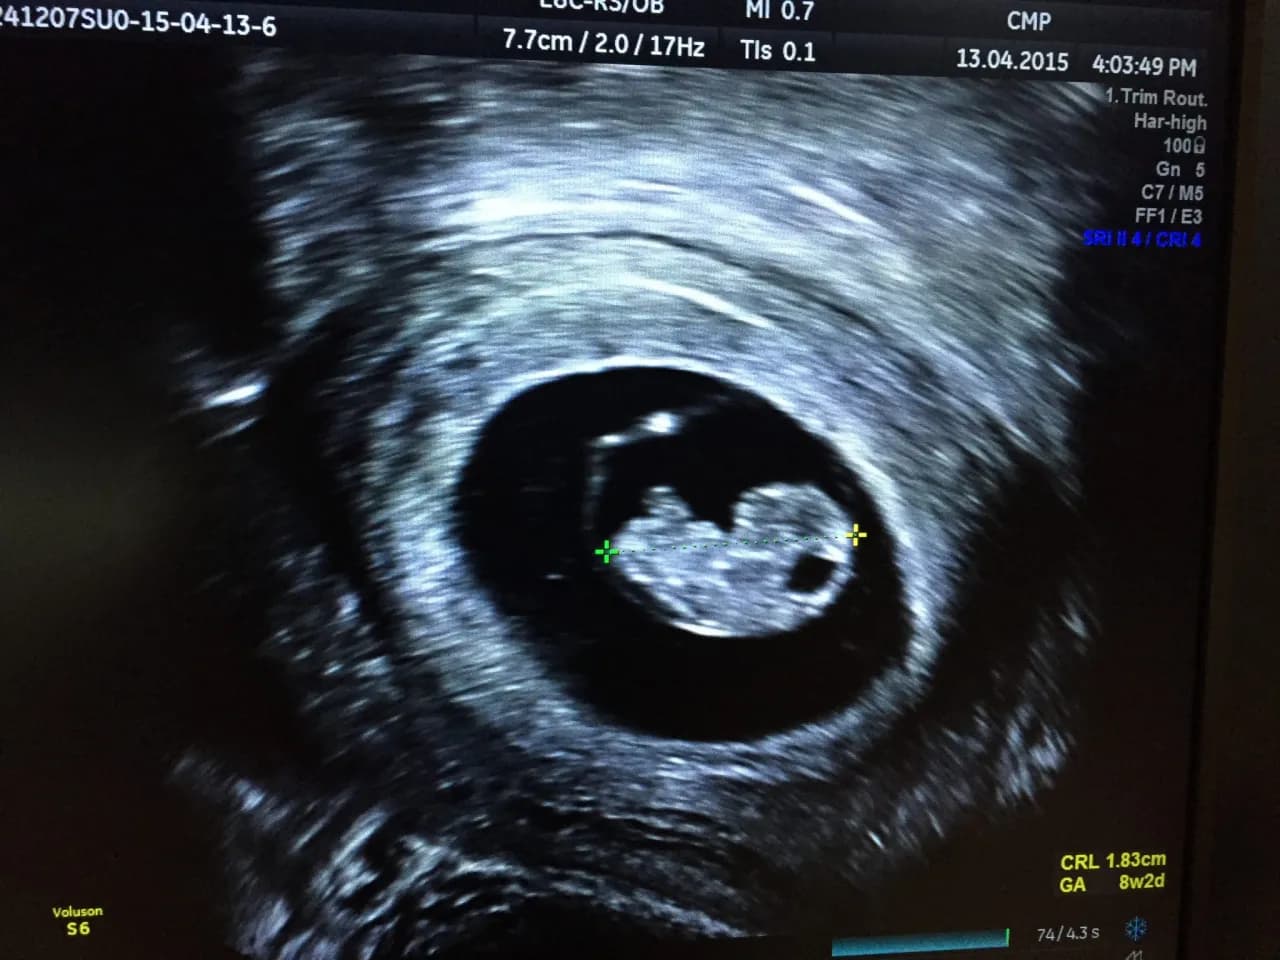

USG w ciąży - co można zobaczyć i kiedy?

Kiedy widać ciążę na USG? Pierwsze oznaki ciąży można zaobserwować w badaniu USG około 4-5 tygodnia od ostatniej miesiączki. W tym czasie widoczny staje się pęcherzyk ciążowy w macicy. To mała, okrągła struktura wypełniona płynem, w której rozwija się zarodek.

Kolejne tygodnie przynoszą więcej szczegółów. Około 6 tygodnia można zobaczyć zaczątek bicia serca. W 8-10 tygodniu widoczne są już zarysy główki i tułowia dziecka. USG dostarcza cennych informacji o rozwoju płodu i przebiegu ciąży.